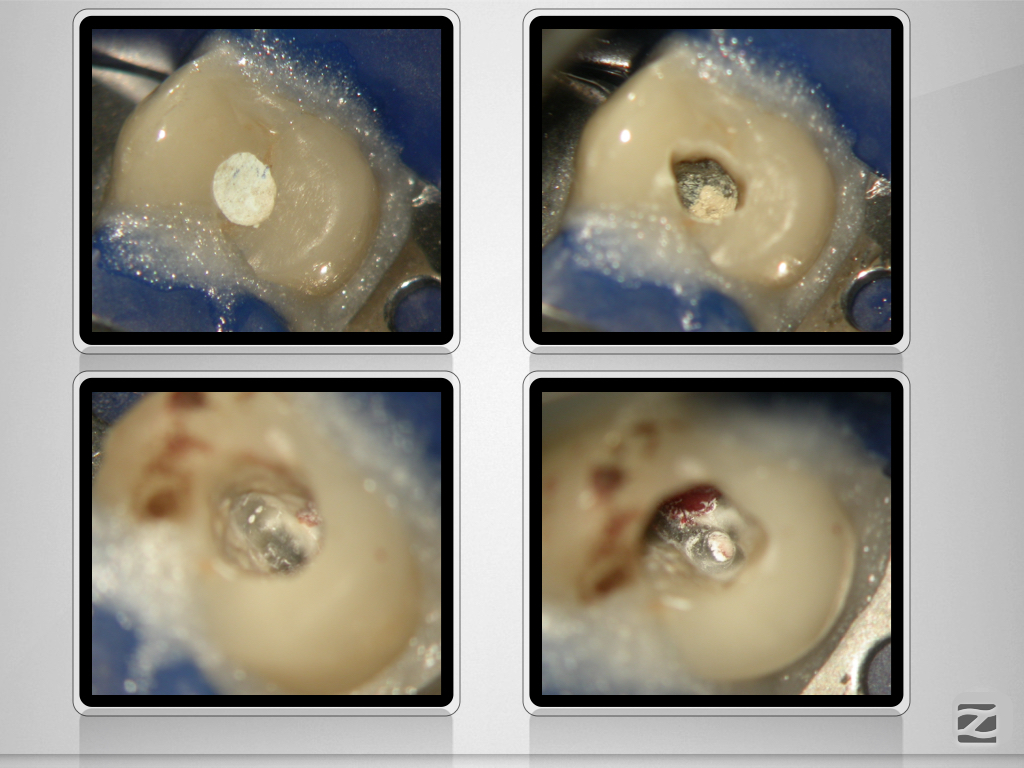

Deutlich verfehlt